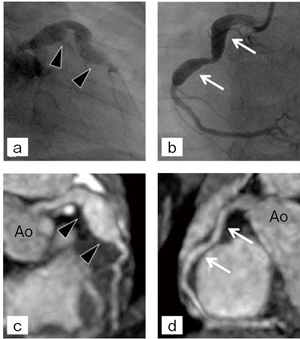

5か月時川崎病発症男児(体重12.1kg,心拍115bpm)。心カテーテル検査を7か月時に施行し,左右冠動脈瘤を認めた。その1か月後の8か月時に,MRIによるMRCAを施行し,左右冠動脈を末梢まで明瞭に描出し,1か月前の心カテーテル検査時から変化を認めた(図4)。

図4 症例1:5か月時川崎病発症男児

a,b:心カテーテル画像